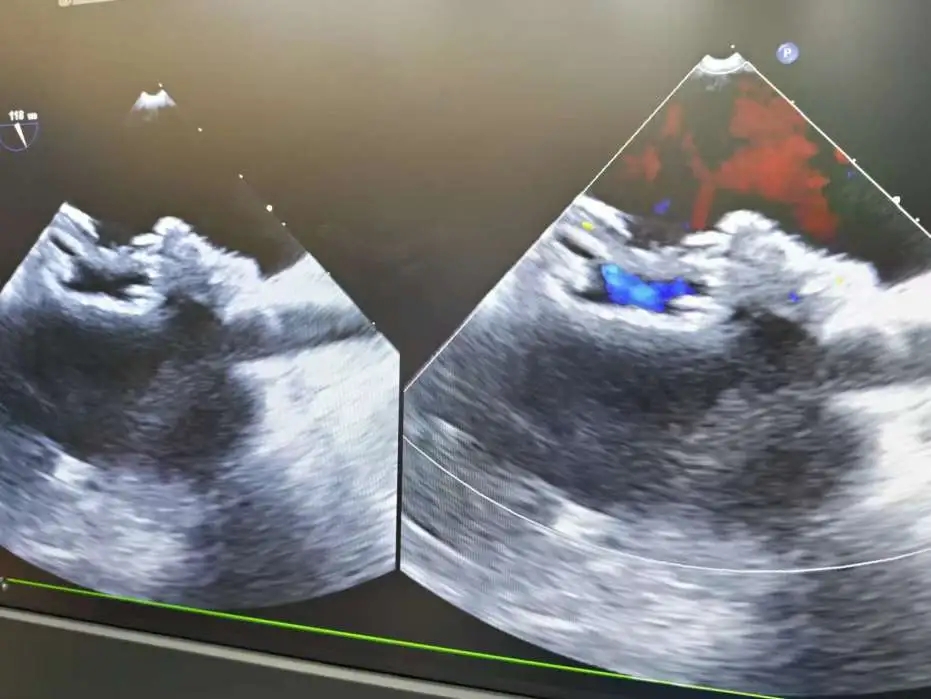

双封堵器释放后超声

CDFI:AR(-),MR(少量),TR(少量)。房间隔中部探及两处封堵器回声,房水平未见明显分流。室间隔连续完整,室水平未见明显分流。肺动脉内径不增宽。升主动脉内径23mm。心包腔内未见明显液性暗区。

《常见先天性心脏病介入治疗中国专家共识》指出:对于存在2个ASD,但缺损间距≤7mm,可选择1枚封堵器闭合;多个缺损的间距>7mm,无法采用1枚封堵器实施介入治疗,需要选择2~3枚封堵器分别闭合[1]。本例食道超声示两处缺损(回声中断8.06mm,分流束宽5.63mm),两个缺损之间相距8.48mm,术中通过超声精准指导,先植入BDASD-I16封堵器封堵8.06mm缺损,再测量第二个缺损约5mm后,植入BDASD-I10封堵器,术后即刻超声显示,两枚MemoSorb可降解封堵器位置形态理想,无残余分流,封堵成功。